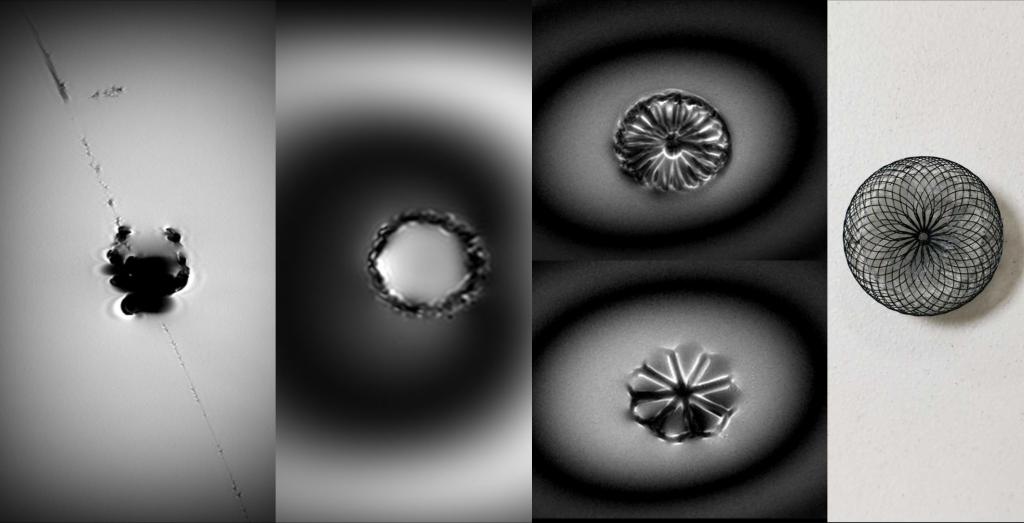

影像中心自成立以来,承担了科技部、国家自然科学基金委、卫生部、北京市科委等近百项国家和省部级项目,收到各种研究经费支持达5000万余元,已发表论文600余篇,发明专利60余项,国际专利10余项,培养学生130余人,获得各种奖励30余项。影像中心已成为全球重要的医学影像尤其是磁共振技术研发中心,开发出大视野高分辨血管壁多对比度成像、三维心肌定量成像、定量血流成像、定量生理成像、无变形高分辨率弥散成像等诸多原创技术,同时这些技术被广泛地应用在多项大规模临床人群队列研究当中形成了针对心脑血管、神经变性性疾病等原创性影像学解决方案。